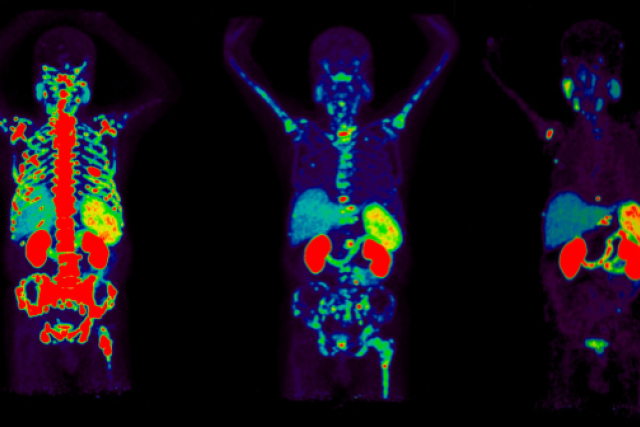

Certain radioisotopes emit radiation which is not harmful to cells and can be imaged using positron emission tomography (PET). This is the diagnostic part of theranostics. Others emit radiation which can damage and even kill cells. This is the therapeutic part.

Theranostics Therapy

In theranostics, doctors administer a specialized molecule called a radiotracer that can hold a radioisotope and target cancer cells. The radiotracer then binds to the cancer, allowing doctors to see exactly where it is and deliver cell-damaging radiation directly to it. This “see what you treat” approach helps doctors diagnose, stage, and treat cancer while minimizing damage to healthy tissues.

Theranostics is performed in an outpatient setting and consists of imaging (diagnostic) and therapy phases separated by several weeks. Two types of radiotracers are used: an imaging radiotracer which contains a radioisotope that can be imaged with PET, and a therapeutic radiotracer which contains a radioisotope that emits cell-damaging radiation. Throughout the entire process, your safety will be our top concern.

• Therapy Phase: To treat the cancer identified in the Diagnostic Phase, your health care team will administer a therapeutic radiotracer in our outpatient clinic. Following administration, you will be closely monitored by your care team for two to three hours, after which you will be able to leave the clinic. The number of therapy cycles you undergo will depend on the disease being treated, but can range from one to six.